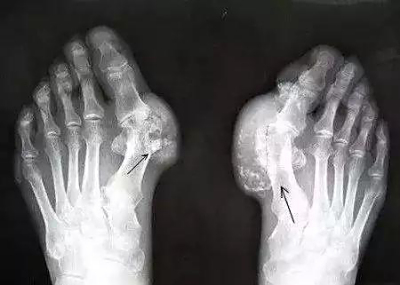

祖传“痛风散”

2021-04-03